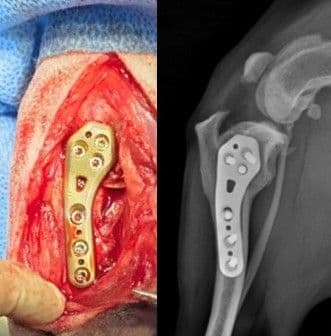

슬개골 탈구 교정술

TTT, DFO, PTO